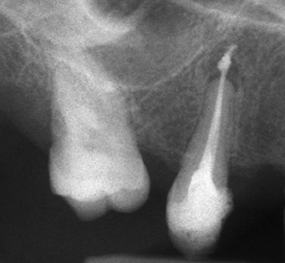

Запълване с препресване

Ендодонтия